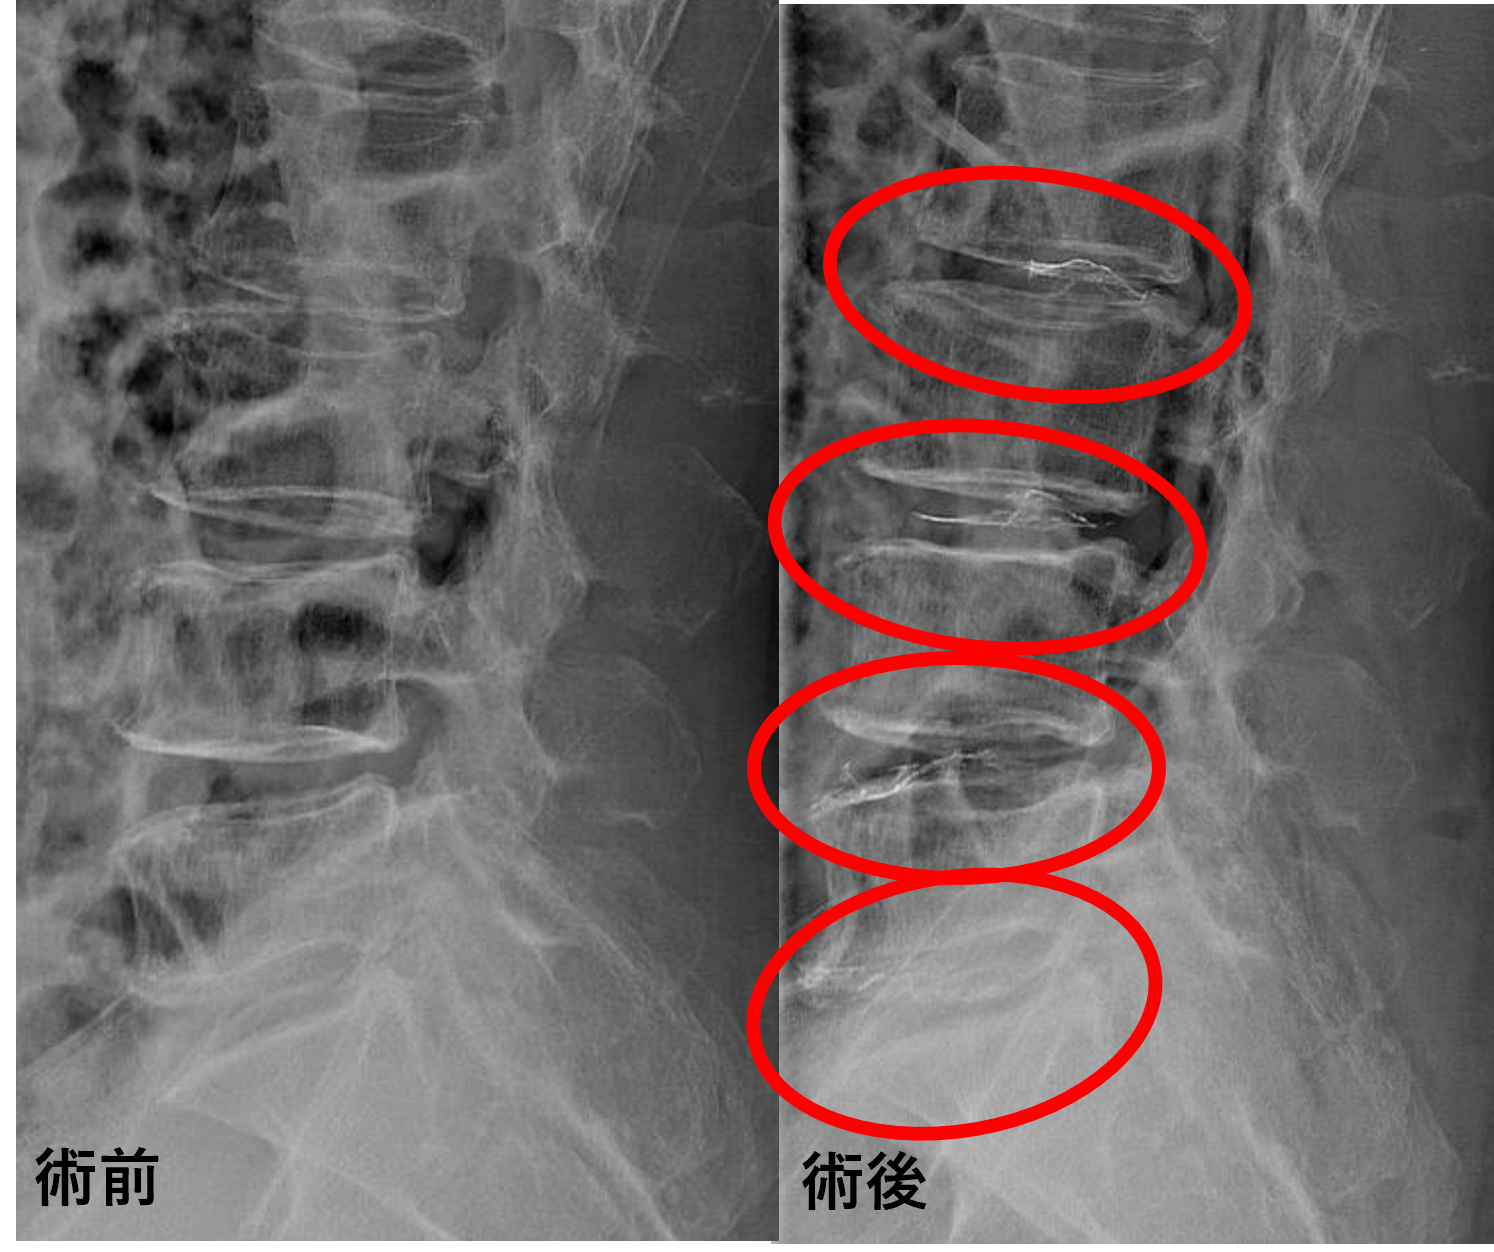

患者様と相談の元、L2/3、3/4、4/5、5/sにセルゲル法を施行

治療は小寺院長が行いました。

治療は30分程度で終了

回復室で休憩後、歩いて帰院されました。